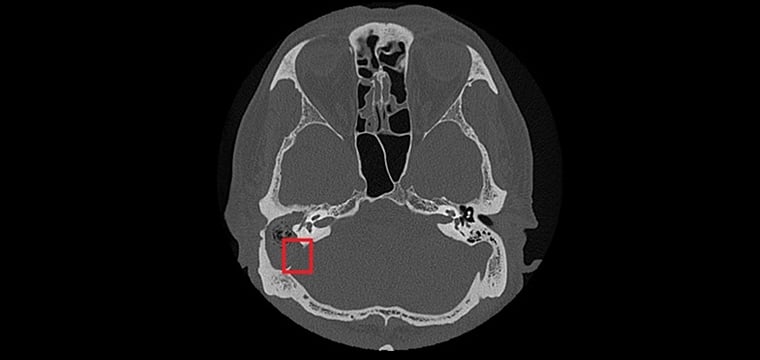

【NOW健康 楊芷晴/新北報導】75歲張先生右耳曾罹患慢性中耳炎並合併耳聾。近日右耳出現耳痛、耳脹並伴隨膿性分泌物,原先於診所治療未見改善,轉至台北慈濟醫院就診時,檢查發現外耳道嚴重紅腫狹窄,內部堆積大量碎屑及膿液。台北慈濟醫院耳鼻喉科鄭靜雯醫師在進行局部清理及藥物治療後,症狀仍未明顯改善,後續更出現右側顏面神經麻痺。經顳骨電腦斷層檢查確認為慢性中耳炎併發膽脂瘤,且病灶已侵蝕顱底骨質,需安排住院治療。

由於膽脂瘤多發生在中耳或接近顱底的位置,一旦形成,可能影響聽力與神經功能,其分泌物亦容易滋生細菌,導致反覆感染;若未及時治療,可能引發暈眩,甚至因鄰近顱內而造成腦膜炎、腦炎或腦膿瘍。目前,手術切除是膽脂瘤根治的唯一方法,術前需以顳骨電腦斷層檢查評估膽脂瘤範圍及侵蝕程度;手術方式依病灶大小、位置,可能採耳內微創、耳前或耳後切開術,徹底清除膽脂瘤並重建受損結構。急性發炎期則需輔以抗生素控制感染,術後追蹤可降低復發風險,但膽脂瘤若已侵蝕骨質,仍需長期觀察。

以張先生為例,雖前後接受過局部藥物、抗生素治療,但考量其慢性中耳炎併發膽脂瘤已破壞聽小骨、乳突及部分顱底骨質,因此需從耳後切開進入外耳道及中耳腔,打開耳後的乳突骨,將病變組織除去後,重建修復骨骼和軟組織缺口。